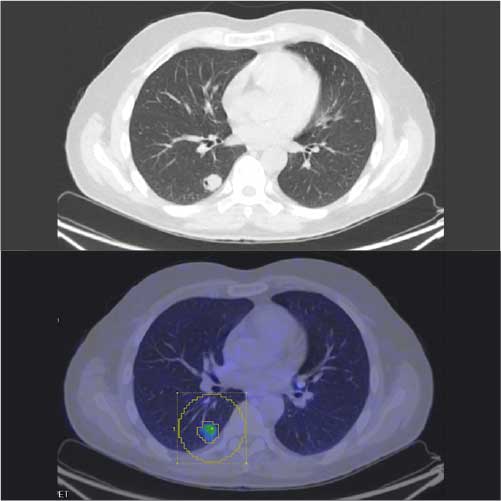

Caso condiviso da Saima Mushtaq

Paziente con anamnesi di malattia coronarica e pregresso impianto di stent sulla discendente anteriore sinistra.

Per prima cosa, esamina l'intera scansione. Concentrati sul tronco comune e sulla porzione prossimale della discendente anteriore sinistra.